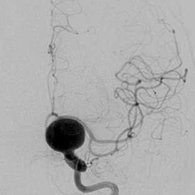

<画像所見>

左眼の奥に大きな動脈瘤認める。

(→動脈瘤)

<手術中の脳血管撮影画像>

瘤(こぶ)は消失